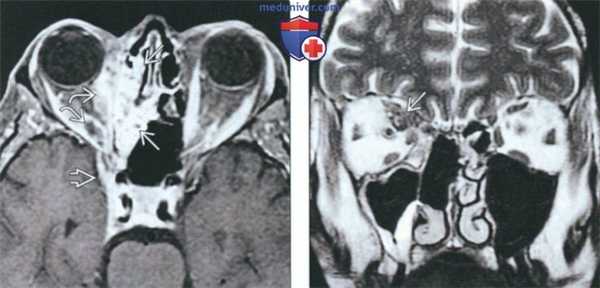

(Слева) На аксиальной МРТ (Т1 ВИ С+) у пациента, получавшего иммуносупрессоры после трансплантации, определяется инвазивный грибковый синусит с поражением ячеек решетчатого лабиринта справа и распространением инфекции в правую глазницу вокруг прямых мышц и с поражением вершины. Определяются также признаки интракраниального распространения через верхнюю глазничную щель.

(Справа) На корональной МР (Т2 ВИ) у этого же пациента в верхних внутренних отделах глазницы определяется гипоинтенсивный сигнал, характерный для грибкового поражения.